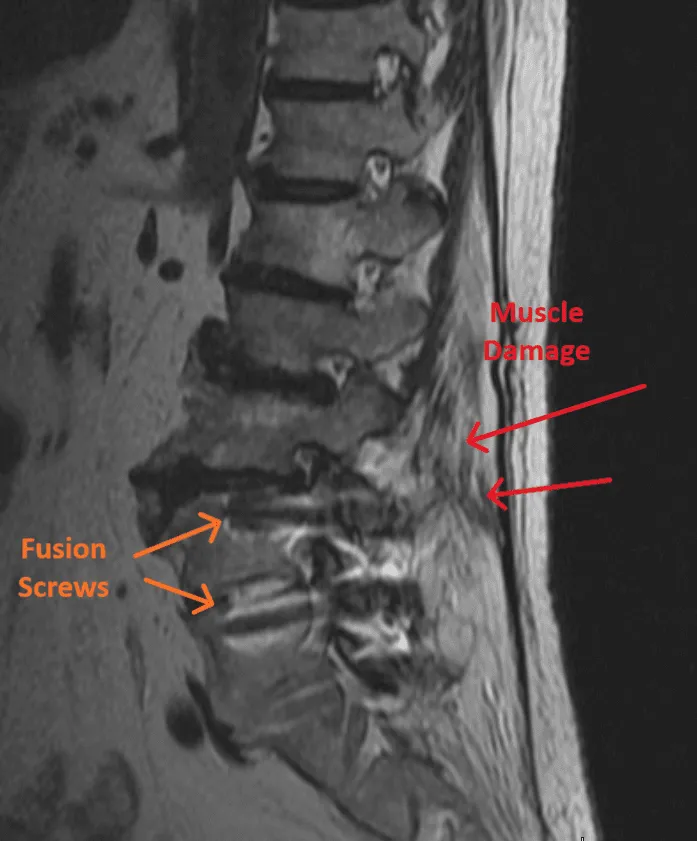

Destroys Spinal Muscles

Spinal muscles are stripped from the bone and retracted, causing permanent damage and weakness.

Hardware Failure

Screw loosening, broken screws or rods, and cage migration requiring revision surgery.